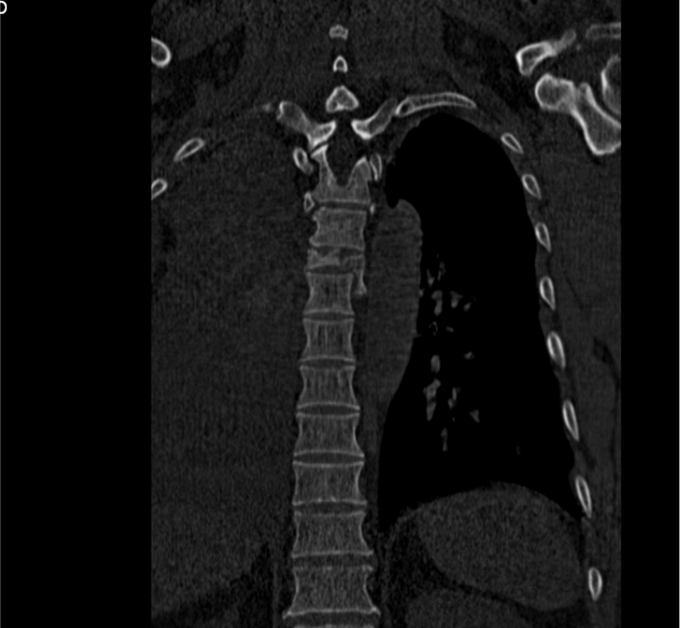

患者于2014-08-13日11:30左右骑摩托车摔倒,伤后一过性意识不清,清醒后感觉胸部疼痛,双下肢活动受限,急诊送至盘锦市宽甸县中心医院,行胸CT、头CT、胸椎三维CT,提示为胸椎骨折,急诊行面部伤口清创缝合,具体治疗不详。患者及家属为求系统治疗,急来我院,急诊予以行辅助检查,提示:胸椎骨折;急诊以“多发外伤”为主诊断收入我科.

诊断:胸3-6椎体骨折,胸髓损伤,双下肢全瘫。 入院后完善检查,查无手术禁忌症后行胸椎骨折后路切开复位椎板减压椎弓根钉内固定术